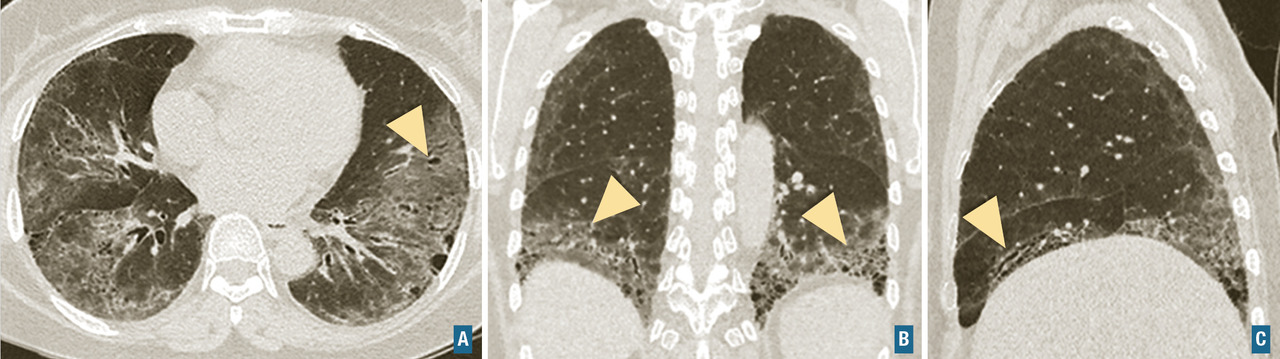

Connectivites

Des éléments évocateurs de connectivite doivent toujours être recherchés, au moins cliniquement lors du bilan d’une pneumopathie interstitielle diffuse. Les connectivites les plus fréquemment impliquées sont la poly­arthrite rhumatoïde, la sclérodermie systémique, le syndrome de Gougerot-Sjögren et les myosites auto­­immunes (dermatomyosite principalement). La présentation scanographique est le plus souvent celle d’une pneumopathie interstitielle non spécifique (fig. 7) qui peut présenter ou non des éléments de fibrose ou des condensations (pneumonie organisée). L’atteinte pulmonaire peut compliquer une connectivite connue ou au contraire être révélatrice de la maladie.

Fibrose pulmonaire idiopathique (FPI) : c’est la plus fréquente et la plus grave des pneumopathies interstitielles diffuses idiopathiques chroniques. Elle est définie par une fibrose progressive et irréversible du poumon, de cause inconnue, et survient le plus souvent chez les hommes dans leur septième décennie, fumeurs ou anciens fumeurs. La médiane de survie après le diagnostic et sans traitement est d’environ 3 ans. Les signes cliniques sont non spécifiques, et incluent une dyspnée d’effort d’apparition progressive, une toux sèche, des crépitants secs, dits « Velcro », précoces et parfois un hippocratisme digital. La fibrose pulmonaire idiopathique est caractérisée par un aspect radiologique et/ou histologique de pneumopathie interstitielle commune. L’aspect scanographique de pneumopathie interstitielle commune associe du rayon de miel, des réticulations sous-pleurales, des bronchectasies et bronchiolectasies de traction (fig. 7). Les anomalies sont de distribution basale et sous-pleurale prédominante, avec un gradient apico-basal. Il existe une alvéolite neutrophilique (10-20 %) ou une discrète éosinophilie au lavage broncho-alvéolaire. Le diagnostic de fibrose pulmonaire idiopathique requiert l’élimination des causes médicamenteuses, d’exposition professionnelle ou domestique et de connectivite, ainsi que la mise en évidence d’un aspect typique au scanner. La biopsie pulmonaire n’est requise que chez les patients dont le diagnostic est incertain et dont la confirmation modifierait l’attitude thérapeutique. L’emphysème fréquemment associé chez les fumeurs modifie la présentation et l’évolution. Il n’existe pas de traitement curatif, la prise en charge actuelle repose sur les médicaments antifibrosants (pirfénidone ou nintédanib) qui ralentissent l’évolution de la maladie. L’évolution clinique peut être émaillée d’exacerbations aiguës accélérant le déclin de la fonction respiratoire et aggravant le pronostic.